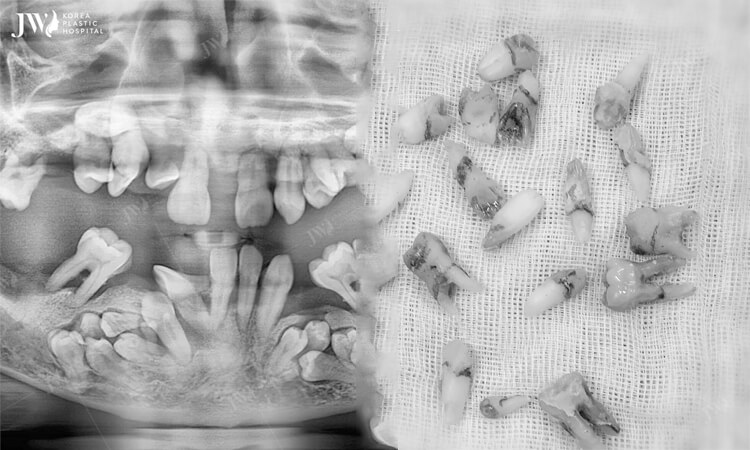

Kinh hoàng bs lấy gần 30 chiếc răng ngầm từ miệng bệnh nhân – U xương hàm mặt

Sáng ngày 20.5.2020 vừa qua, bệnh viện JW tiếp nhận một trường hợp bệnh nhân nam đến điều trị sâu răng. Tuy nhiên, khi tiến hành chụp CT chẩn đoán, các bác sĩ cũng như bệnh nhân lại hoảng hốt khi phát hiện có đến hơn 20 chiếc u răng ngầm mọc dưới xương hàm […]